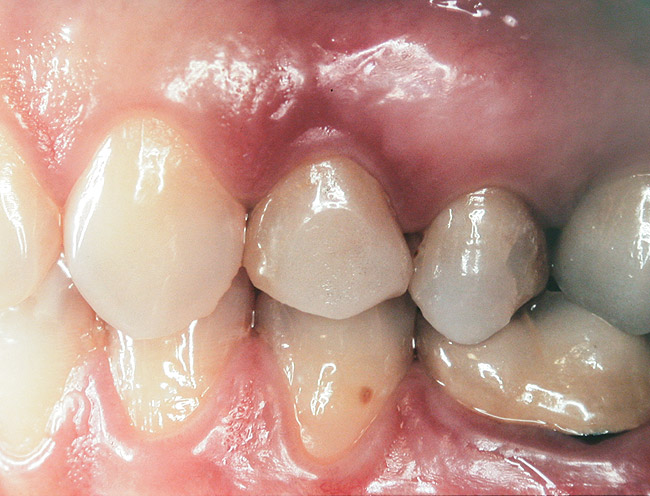

Case 2

A 55-year-old male was referred for implant placement and prosthetic rehabilitation in the area of tooth No. 15. The tooth had been extracted 4 years prior. The radiograph revealed inadequate bone height for implant positioning (Figure 6). It was decided to insert an implant that was 11.5 mm in length and 3.75 mm in diameter, performing a slight osteotomic maxillary sinus lift. A heterologous bone graft also was planned to obtain a larger sinus lift.

A full-thickness mucoperiosteal flap was raised, and alternating osteotomes were used to prepare the implant site. After achieving a length of 7 mm (Figure 7A and Figure 7B), heterologous bone graft was implanted and the osteotome sequence was repeated. The implant showed primary stability.

Second-stage surgery was performed after 4 months (Figure 8); healing abutments were placed and the soft tissue was allowed to heal for 5 more weeks. Then, splinted porcelain-fused-metal (PFM) crowns supported by custom gold abutments were delivered (Figure 9 and Figure 10).

Figure 9  Final implant-supported PFM restorations.

Figure 9